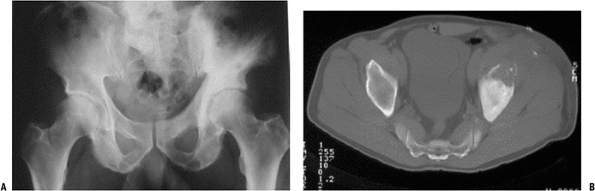

Figure 6.1-2 (A)

Plain radiograph shows an area of bony destruction in the anterior left

iliac wing and pagetic changes throughout the left hemipelvis. (B)

Axial CT image shows lesion with soft tissue extension consistent with

an osteosarcoma secondary to Paget’s disease of the pelvis. -

Paget’s osteosarcoma (Fig. 6.1-2)